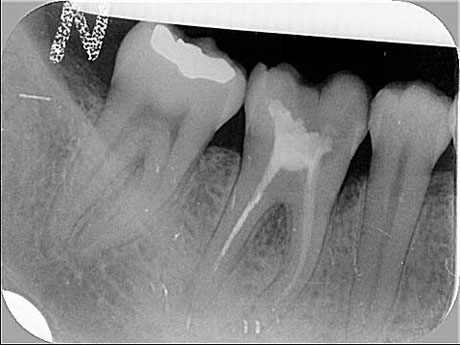

La paziente presentava il molare inferiore destro (il 46) da estrarre per frattura della corona e della radice.In anestesia locale, si procede alla rimozione del molare fratturato e, contestualmente, all'inserimento di un impianto dentale immediato che sostituisce la radice estratta.

Viene anche effettuato un piccolo innesto di osso per migliorare il sostegno dei tessuti molli (gengiva) periimplantari.

L'innesto è coperto da membrana in doppio strato per proteggerlo dal riassorbimento fisiologico.

La gengiva viene suturata e l'impianto risulta transmucoso (cioè, si vede la testa del pilastro di guarigione a filo della gengiva).

La guarigione del tessuto osseo perimplantare richiede tre mesi perché occorre dare tempo all'organismo di formare nuovo osso, dove sono state estratte le radici del molare; infatti l'impianto non ha la stessa forma delle radici rimosse.